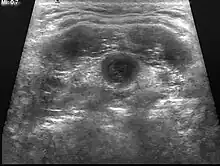

Ultrasound image of thyroglossal duct cyst

Diagnosis of a thyroglossal duct cyst requires a medical professional, and is usually done by a physical examination. It is important to identify whether or not the thyroglossal cyst contains any thyroid tissue, as it can define the degree of cyst that is being dealt with.[9]

Ultrasound Image capture of the degree of mass and its surrounding tissues.